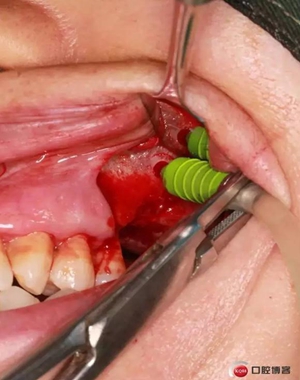

改良式外提升工具盒-外提 科貿(mào)嘉友收錄

六個(gè)月之后